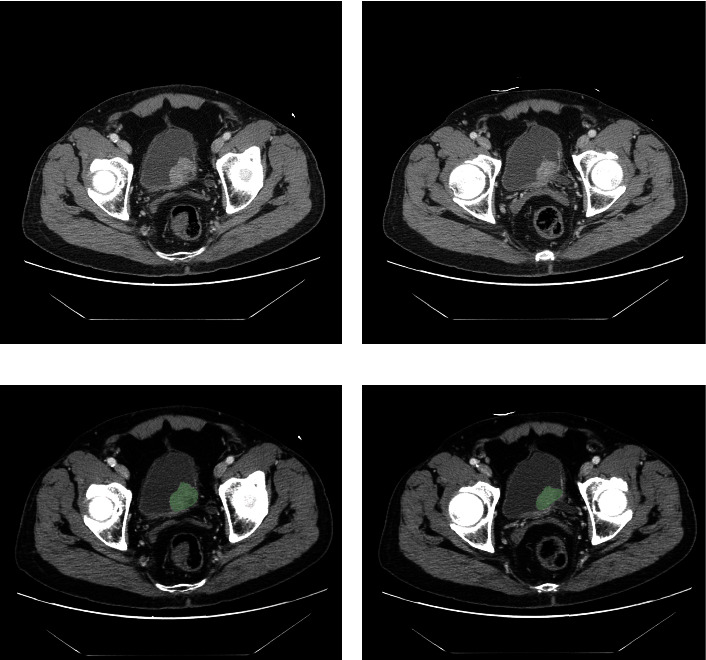

Bladder cancer has recently seen an alarming increase in global diagnoses, ascending as a predominant cause of cancer-related mortalities. Given this pressing scenario, there is a burgeoning need to identify effective biomarkers for both the diagnosis and therapeutic guidance of bladder cancer. This study focuses on evaluating the potential of high-definition computed tomography (CT) imagery coupled with RNA-sequencing analysis to accurately predict bladder tumor stages, utilizing deep residual networks. Data for this study, including CT images and RNA-Seq datasets for 82 high-grade bladder cancer patients, were sourced from the TCIA and TCGA databases. We employed Cox and lasso regression analyses to determine radiomics and gene signatures, leading to the identification of a three-factor radiomics signature and a four-gene signature in our bladder cancer cohort. ROC curve analyses underscored the strong predictive capacities of both these signatures. Furthermore, we formulated a nomogram integrating clinical features, radiomics, and gene signatures. This nomogram's AUC scores stood at 0.870, 0.873, and 0.971 for 1-year, 3-year, and 5-year predictions, respectively. Our model, leveraging radiomics and gene signatures, presents significant promise for enhancing diagnostic precision in bladder cancer prognosis, advocating for its clinical adoption.

Abstract Image